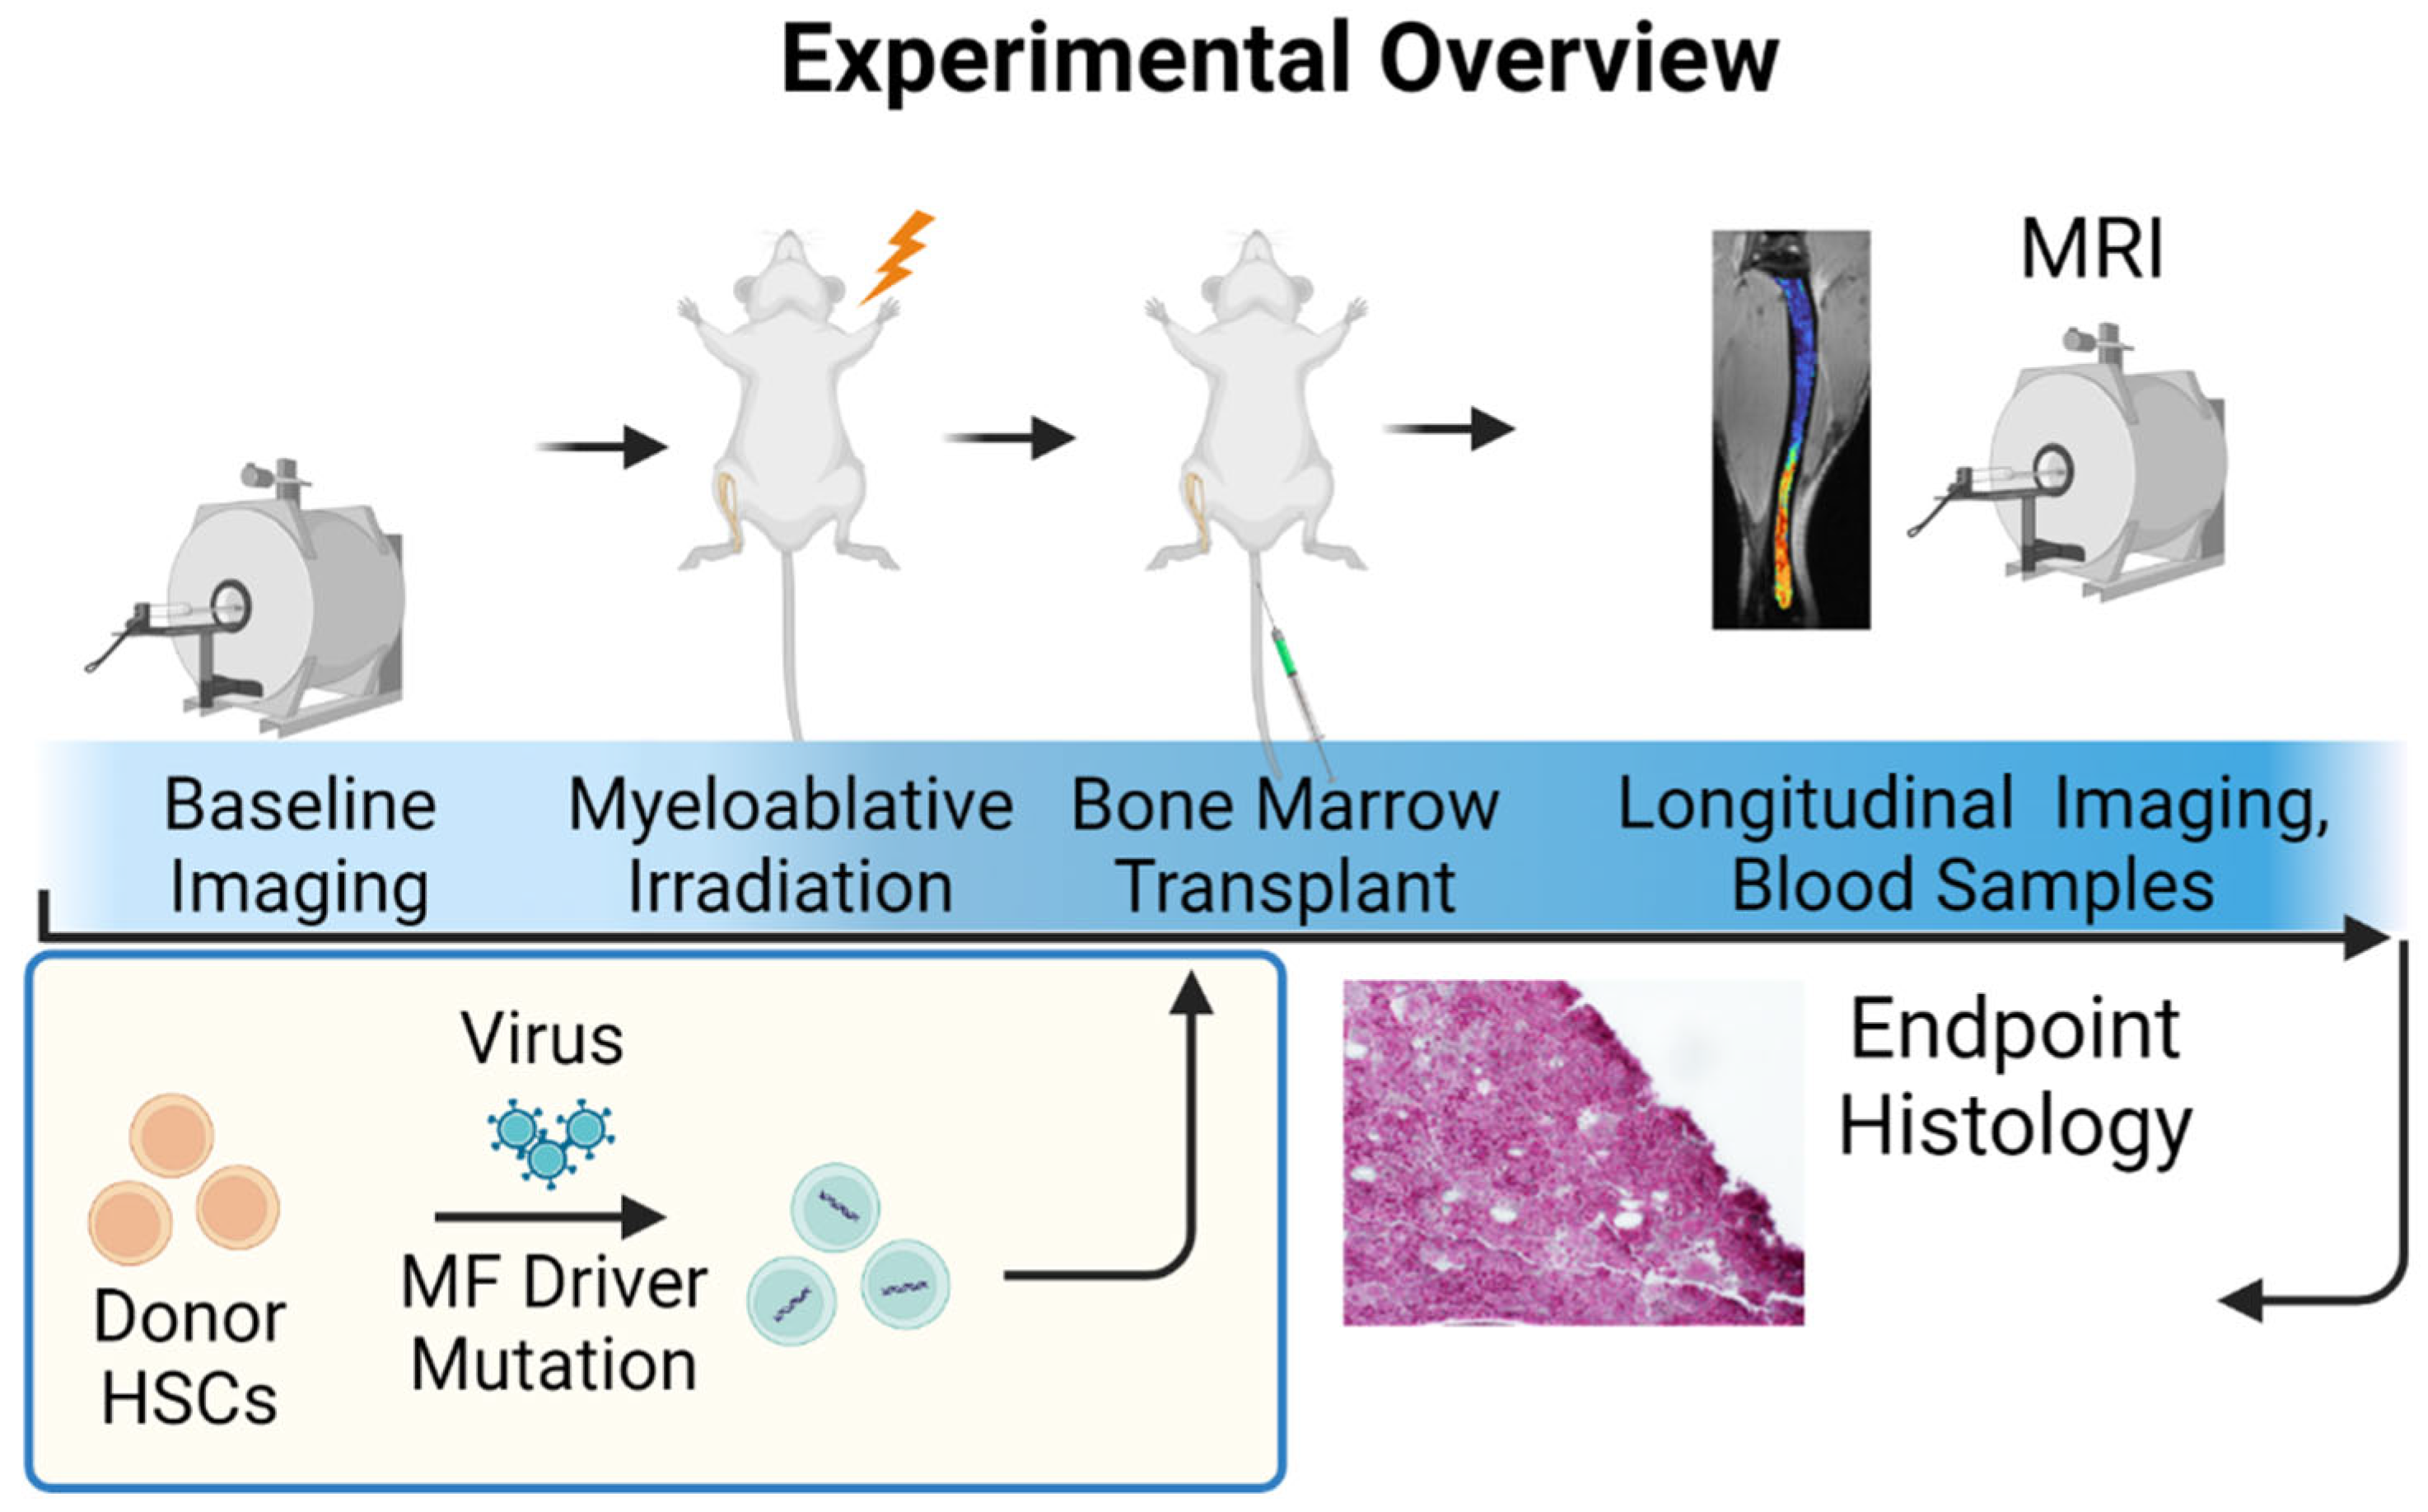

2.6. University of Michigan Quantitative Bone Marrow MRI in Myelofibrosis

- Ross, B.D.; Jang, Y.; Welton, A.; Bonham, C.A.; Palagama, D.S.W.; Heist, K.; Boppisetti, J.; Imaduwage, K.P.; Robison, T.; King, L.R.; et al. A Lymphatic-Absorbed Multi-Targeted Kinase Inhibitor for Myelofibrosis Therapy. Nat. Commun. 2022, 13, 4730. [Google Scholar] [CrossRef]

- Robison, T.H.; Solipuram, M.; Heist, K.; Amouzandeh, G.; Lee, W.Y.; Humphries, B.A.; Buschhaus, J.M.; Bevoor, A.; Zhang, A.; Luker, K.E.; et al. Multiparametric MRI to Quantify Disease and Treatment Response in Mice with Myeloproliferative Neoplasms. JCI Insight 2022, 7, e161457. [Google Scholar] [CrossRef]